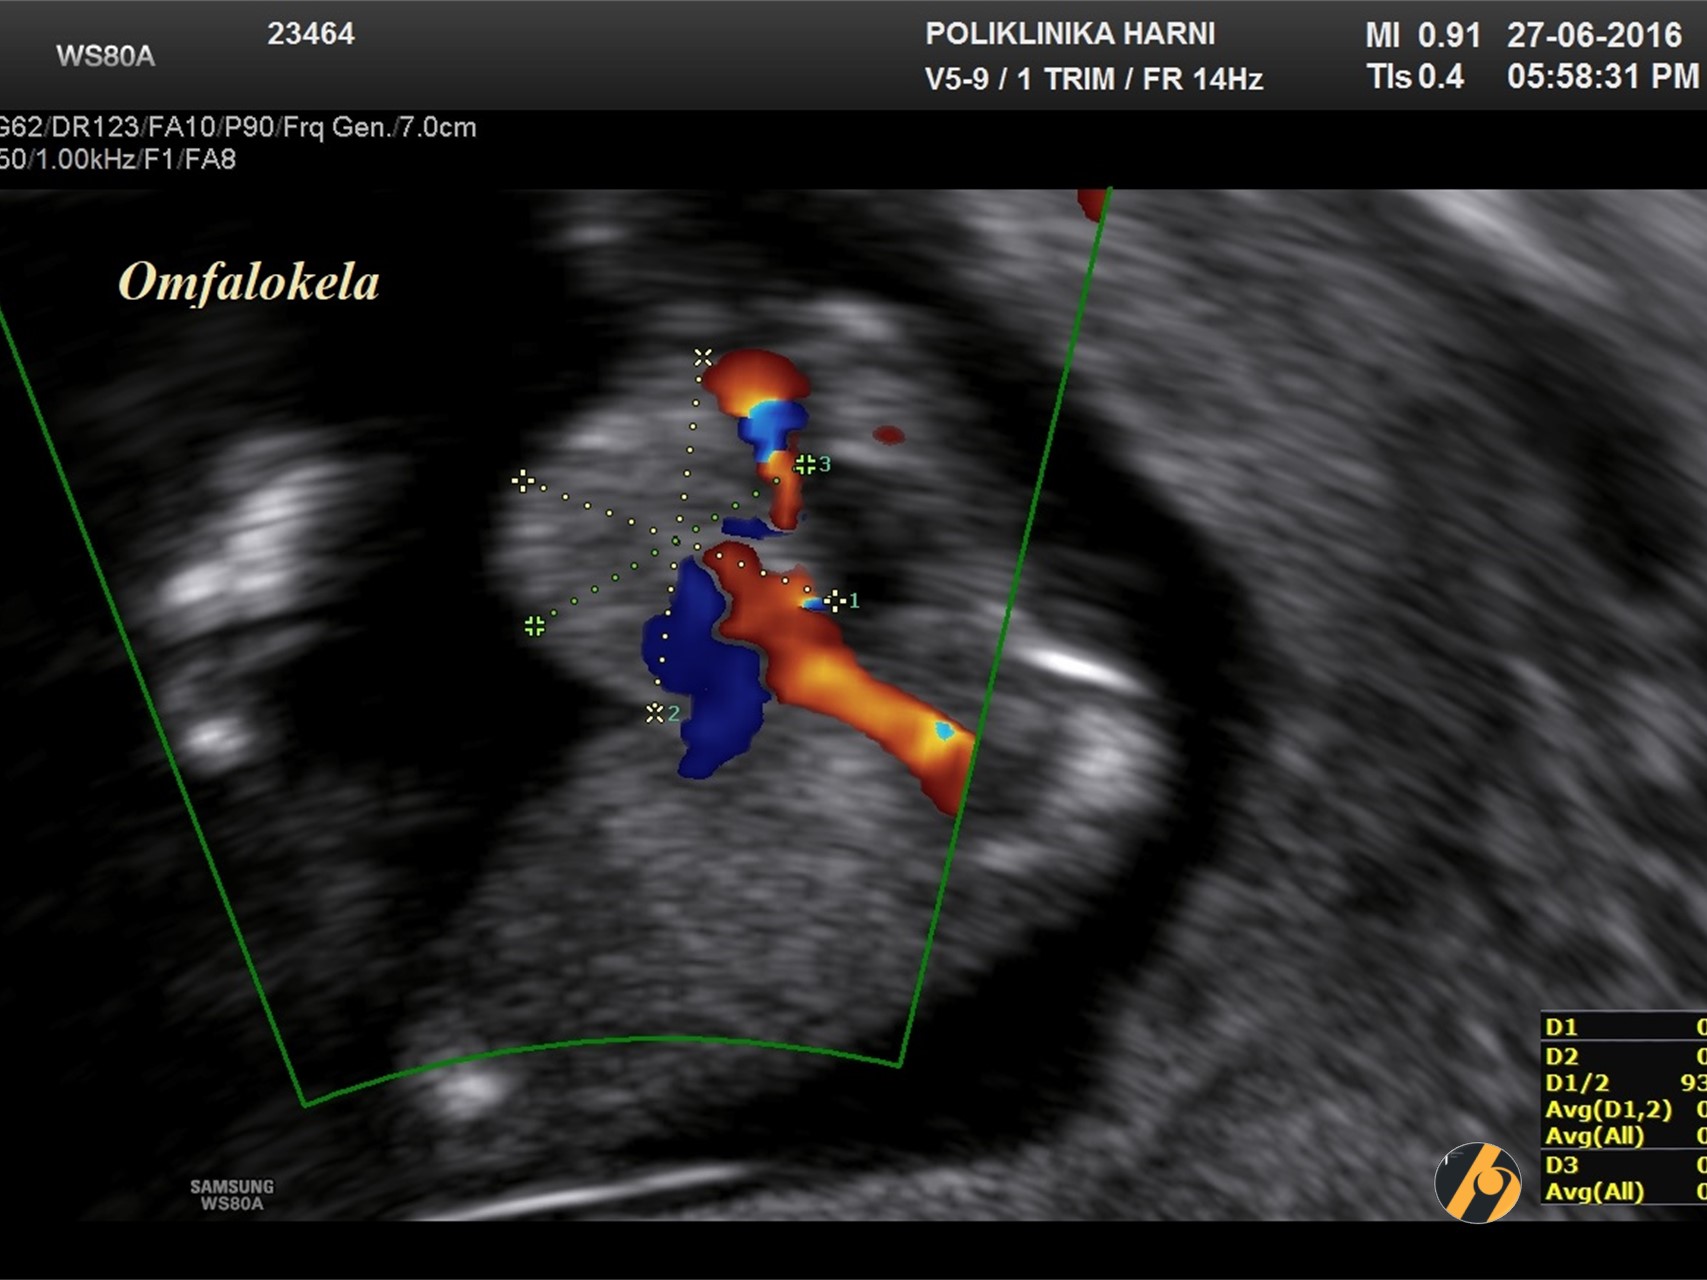

S 8-10 tjedana svi fetusi pokazuju hernijaciju tankog crijeva koja se vizualizira kao hiperehogena masa u bazi pupkovine. Retrakcija u abdomen se događa između 10.-12. tjedna trudnoća, a završava do 11 + 5 tjedana.

U 11.-13. tjednu trudnoće pojavnost omfalocele je oko 1 na 1,000, što je četiri puta veće nego kod živorođenih. Stanje je obično sporadično. Učestalost kromosomskih anomalija, uglavnom trisomije 18, iznosi oko 60%, u usporedbi s 30% u sredini trudnoće i 15% u novorođenčadi, jer je trisomija 18 povezana s velikom stopom intrauterine smrti.

Rizik kromosomskih anomalija je veći ako omfalocela sadrži samo crijevo bez jetre. Povećani nuhalni nabor nalazi se u otprilike 85% kromosomski nenormalnih i 40% kromosomski normalnih fetusa s omfalocelom.

Na slici je prikazana omfalokela u 12. tjednu trudnoće, udružena s generaliziranim fetalnim edemom.